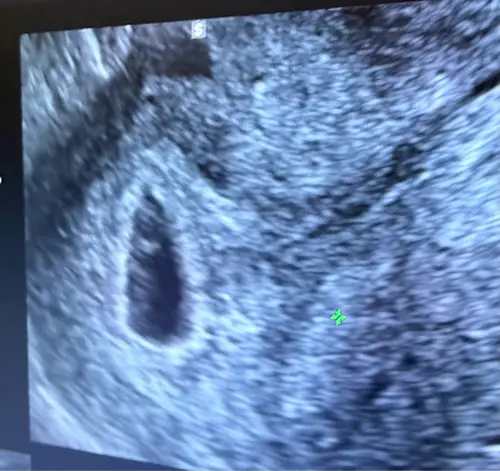

Hoi allemaal, Ik ben 6+1 weken zwanger na IVF. Op de echo was een vruchtzak en dooierzak te zien, maar nog geen hartactie. De arts zegt dat het nog pril is en alle kanten op kan gaan. Volgende week heb ik weer een echo (7+2). Zijn er mensen die rond 6 weken ook nog geen hartje zagen maar later wel? Ik hoor graag jullie ervaringen 🤍